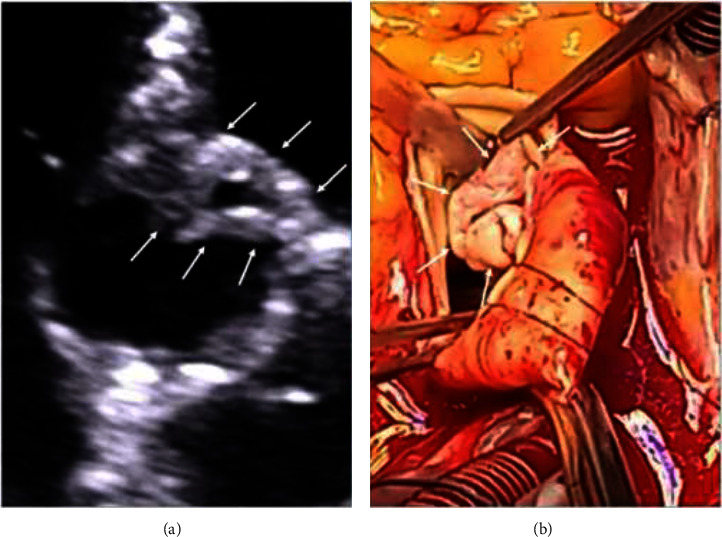

Introduction: Broviac catheter is a type of central venous catheter (CVC) used for long-term parenteral nutrition in specific patients, e.g., diagnosed with intestinal failure as short bowel syndrome (SBS). The way of the catheter insertion is conceived to minimalize the risk of infections. However, CVC-related blood stream infections (CVC-BSIs), including infective endocarditis (IE), remain most important complications associated with Broviac catheter. Staphylococcus epidermidis stands out as a prevalent pathogen. The increasing number of CVCs results in an increased incidence of healthcare-associated IE. Complete parenteral treatment is an independent risk that increases the likelihood of IE. Treatment of IE is mainly based on antibiotic therapy, but in certain cases, surgical treatment is needed. Presentation of Case: A 71-year-old female with SBS who had been receiving total parenteral nutrition through the Broviac catheter for several months was admitted in a serious condition with significant weakness, increasing shortness of breath, deteriorating cough, fever, low blood pressure, and heart palpitations. Echocardiography revealed severe aortic valve IE with a large, longitudinal, highly mobile vegetation (up to 40 mm) and massive aortic regurgitation with pulmonary edema. Fast pathogen detection in the patients' blood (S. epidermidis) was obtained using PCR-based multiplex test. Due to life-threatening conditions, emergency surgery with aortic valve replacement was performed. Consistent rehabilitation resulted in good condition achievement. Follow-up echocardiography showed normal function of the aortic valve bioprosthesis. Conclusion: The use of CVC, including Broviac catheter, is associated with an increased risk of infections, including IE. Treatment-resistant severe HF complicating IE requires emergency surgery.